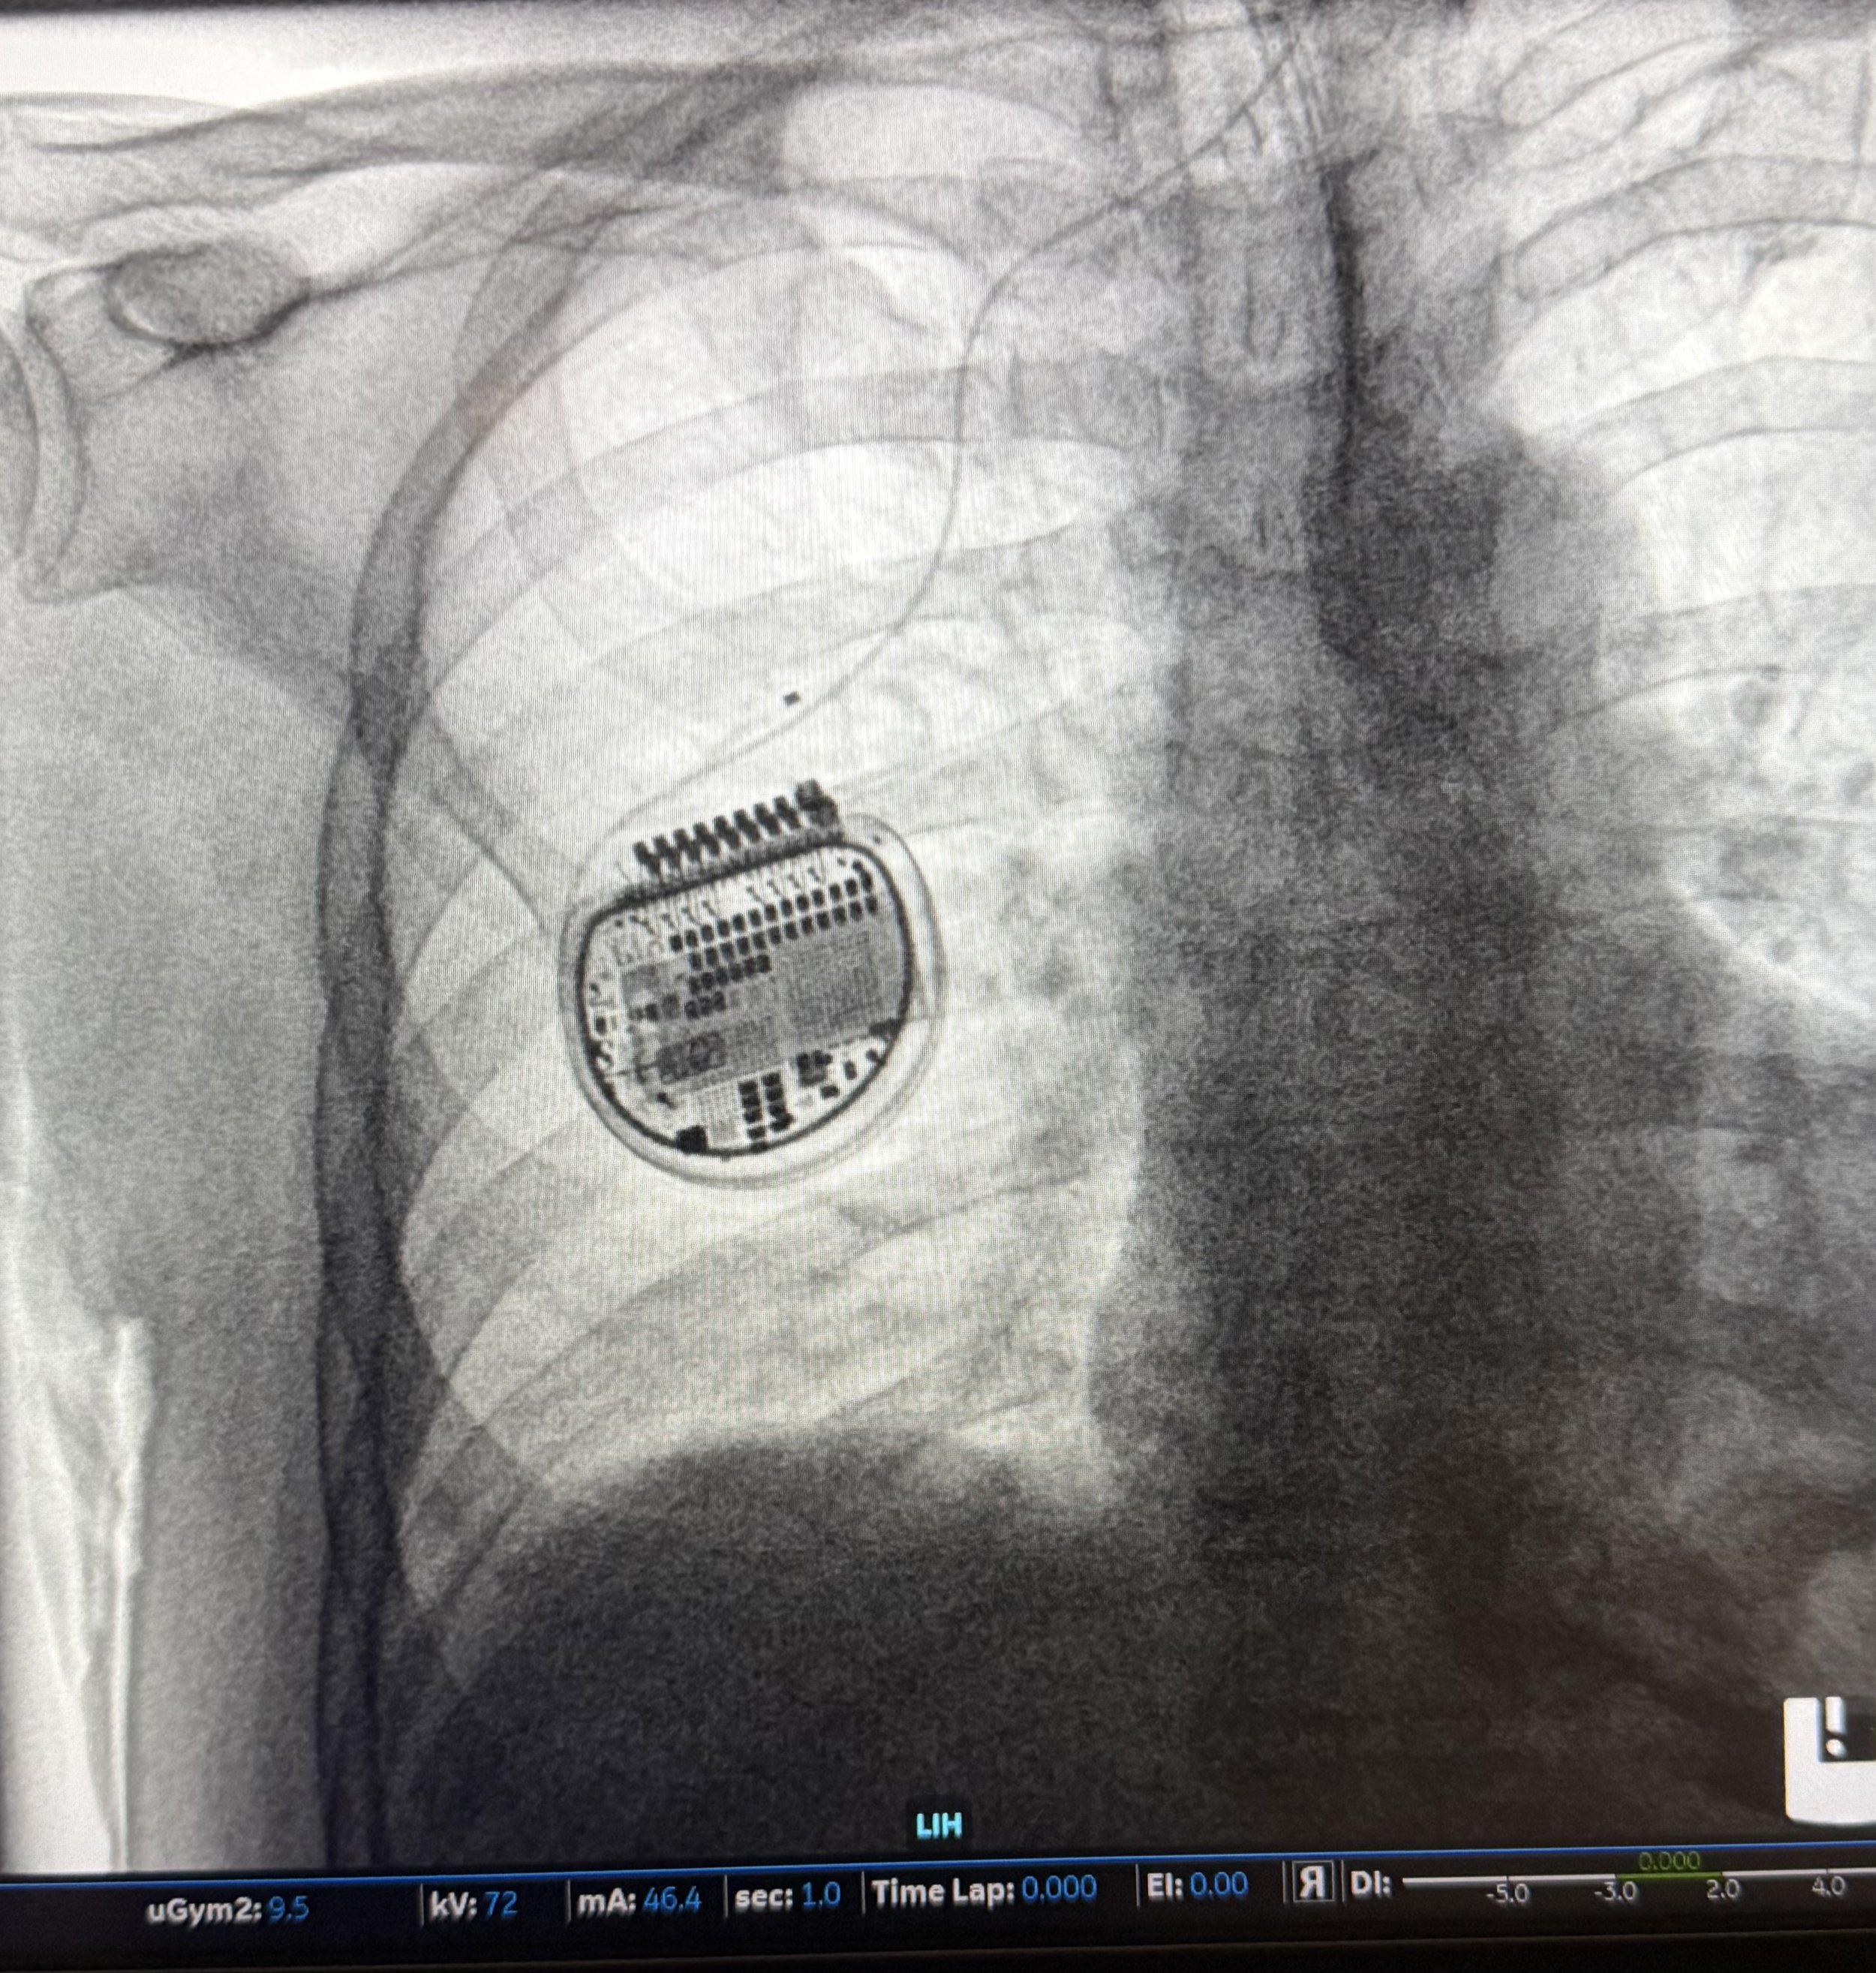

For Parkinson's patients whose symptoms have moved beyond what medication alone can manage, there's an advanced option called deep-brain stimulation, or DBS. In the procedure, a small device is implanted that delivers gentle electrical signals to specific areas of the brain responsible for movement. Think of it like a pacemaker — but for the brain. It doesn't cure Parkinson's, but for many patients it significantly reduces tremors, stiffness, and the other physical symptoms that make daily life so difficult.